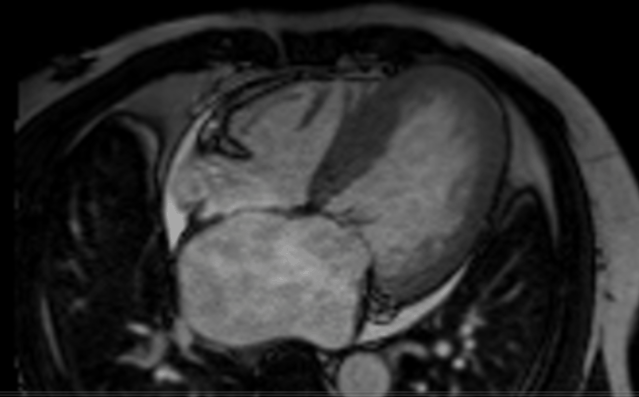

MRI是可以把房顶拆掉看内部结构。

心脏MRI可以对心脏彩超做出补充,对于心肌细胞的水肿、心肌炎与急性心肌梗死的鉴别等方面优势明显。